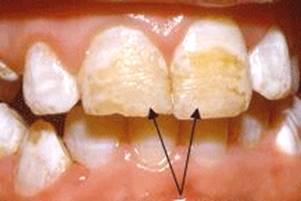

(симметрично расположенные пятна белого цвета на одноименных зубах)

Этиологическим фактором гипоплазии эмали считают недостаточную или замедленную функцию одонтобластов, что возникает в связи с нарушением обмена во всём организме под влиянием различных заболеваний или в результате нарушения обмена в отдельных фолликулах под влиянием механической травмы, инфекции, проникающей радиации и др. В зависимости от действующей причины нарушение возникает в группе зубов, формирующихся в один и тот же период (системная гипоплазия); на нескольких рядом стоящих зубах одного или разного периода развития (очаговая гипоплазия); на одном или нескольких зубах (местная гипоплазия). Системная гипоплазия составляет 90,6% поражений такого рода. Системная гипоплазия эмали встречается в 2-14% случаев, характеризуется нарушением развития эмали во всех или группе зубов одновременно. Гипоплазия эмали встречается у 12-19% детей, что подтверждают данные литературы. Дефекты гипоплазии локализуются на симметрично расположенных зубах, в одном и том же участке коронок, с очагом поражения одинаковой ширины, то есть клиническое её проявление одинаково на всех зубах. На молочных зубах она встречается редко, в основном как результат нарушения обмена в организме беременной женщины и крайне редко вследствие нарушения обмена у ребёнка в первые месяцы жизни. Нередко гипоплазия сочетается с врождённой аллергией, характеризующейся нарушением водно-минерального обмена. Гипоплазия возникает также у детей, перенёсших поражение ЦНС, переболевших гемолитической желтухой на фоне резус-конфликта, рахитом, тетанией, желудочно-кишечными заболеваниями, имеющих поражение эндокринной системы, у искусственно вскармливаемых, при врождённом сифилисе.

Пятна, бороздки и гнезда

Как уже говорилось, основным клиническим проявлением гипоплазии является изменение внешнего вида зуба. Существует несколько форм поражения. Гипоплазия может проявляться в виде белых пятен (пятнистая форма), чашеобразных углублений округлой формы (эрозивная форма), в виде одиночных или множественных бороздок (бороздчатая и волнистая форма).

По локализации участка гипоплазии можно судить о возрасте, в котором происходит нарушение минерального обмена, а по ширине участка поражения определяют длительность нарушения. По количеству участков гипоплазии, располагающихся параллельно режущему краю, уточняют, сколько раз возникало нарушение обмена в организме ребёнка. Следует отметить, что более 60% дефектов гипоплазии развиваются в первые 9 месяцев жизни ребёнка, когда ещё слабо выражены компенсаторные и адаптационные механизмы, и любые неблагоприятные факторы (болезнь, неправильное питание) могут вызывать нарушение обмена в организме (Дьякова С,В., 1965). Поэтому гипоплазия чаще встречается в области режущего края резцов, клыков и буфов первых моляров. При заболеваниях детей на протяжении 3-4 года жизни гипоплазия проявляется в остальных зубах. При этим поражаются коронки зубов вплоть до пришеечной области, а у премоляров и вторых моляров пятна могут быть на жевательной поверхности.